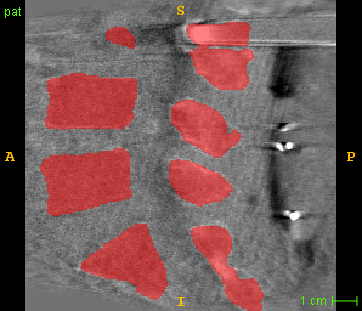

2D segmentation. Our model is compared with two methods based on domain adaptation: AdaptSegNet [16] and SIFA [2]. AdaptSegNet and SIFA are trained with the officially released codes. AdaptSegNet is trained with Dice loss as we only have one class here. The results are summarized in Fig. 6 and Table 2(a). AdaptSegNet invokes DeeplabV2 as the segmentor and cannot capture the vertebra especially when metal artifacts exist. SIFA outputs plausible predictions but the performance is heavily affected by the metal artifacts. Also, the segmentations predicted by SIFA can not capture vertebrae precisely and show false positive bones and enlarged masks (see red arrows in Fig. 6). With joint learning, our model achieves the best segmentation performance with an average Dice of 0.847 and an average ASD of 1.54mm.

Modality translation and artifact reduction. Here we compare our model with other methods: CycleGAN [21], DRIT [8], ADN [9]. All the models are trained with our data using their officially released codes. Further, we train a UNet segmentation network using annotated CT data and apply it to synthesized CT images as an anatomy-invariant segmentation evaluator. As shown in Table 2(b), our model achieves the best performance with a much larger average Dice compared with other methods. Fig. 6 shows the synthetic images and segmentation results. CycleGAN and DRIT tend to output plausible and realistic CT images but are not able to preserve the anatomical information precisely. As shown by the red arrows in Fig. 6, the bony structures appear distorted and noisy. ADN can retain most of the anatomical information but not for the bone pixels with high intensity, which might be classified into metal artifacts. With anatomical knowledge learned from the CT domain, our model outputs high-quality synthetic CT images while keeping anatomical consistency.

For artifact reduction, ADN and DRIT [8] could not successfully recover the clean images and streak artifacts remain in the synthetic image (see blue arrows in Fig. 6). CycleGAN [21] could output clean images but the distorted bones make them less valuable. Our model can suppress all the artifacts and keep the bone edges sharp, which outperforms all the other methods.